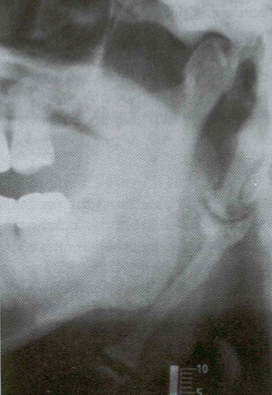

Eagle’s Syndrome (Or Stylohoid Syndrome and Carotid Artery Syndrome)